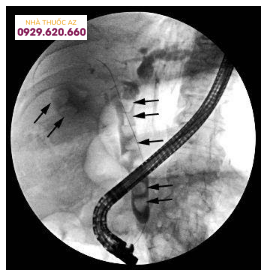

Sốc nhiễm trùng đường mật do sỏi ống mật chủ

Các nguy cơ của phẫu thuật nên được giải thích cẩn thận cho bệnh nhân và gia đình. Từ những kinh nghiệm của các nhà nội soi, có thể đem lại sự sống và làm giảm thiểu các nguy cơ với sự hỗ trợ của thầy thuốc trong công tác săn sóc ban đầu về nhiễm trùng đường mật.Điều trị viêm tụy cấp do sỏi qua nội soi:Trước đây khi nói về nguyên nhân viêm tụy cấp (viêm tụy cấp), các nguyên nhân chưa tìm thấy được xếp vào nhóm vô cằn. Ngày nay quan niệm này đã thay đổi, gây viêm tụy cấp thông thường nhất là sỏi mật, kế đó là do rượu, những nguyên nhân khác ít gặp hơn như do chuyển hóa, do chấn thương, do dị dạng bẩm sinh hoặc do ký sinh trùng vào đường tụy.Bệnh nguyên thông thường được chấp nhận nhiều nhất trong viêm tụy cấp là thuyết “tắc nghẽn”. Ống tụy và ống mật được nối chung bởi một đoạn ngắn trước khi đổ vào tá tràng, một khi có 1 viên sỏi mật nhỏ chạy ngang và kẹt ngay tại phần chung này sẽ làm ngừng chảy dịch tụy và gây hiện tượng trào ngược dịch mật vào tụy. Chính do tác động phá hủy men tụy này sẽ gây viêm tụy cấp.